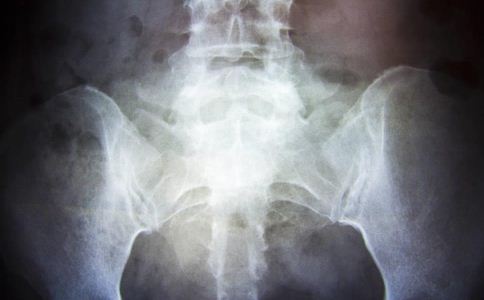

經過一系列檢查,終於找出阿豪的病根是主動脈狹窄。CT三維重建顯示,患者降主動脈有一段嚴重狹窄,解除血管狹窄,就能緩解高血壓。中山二院心胸外科王銘輝副教授為阿豪做了“主動脈人工血管旁路移植術”,將原有的血管保留,用人工血管新增一條向下的運輸通道。手術之後,阿豪的血壓也恢復到了正常水平。

手術醫生,王銘輝介紹,阿豪的高血壓是典型的“繼發性高血壓”,“因為降主動脈狹窄,心髒泵出的血壓流入腹主動脈的分量變少,相應地進入上肢和頭部的增加,”王銘輝說,“所以,就會出現上下肢血壓差異,阿豪的上肢血壓很高,結果經常頭暈、頭痛,而下肢的足背動脈搏動卻很弱,幾乎摸不到,導致下肢無力。”